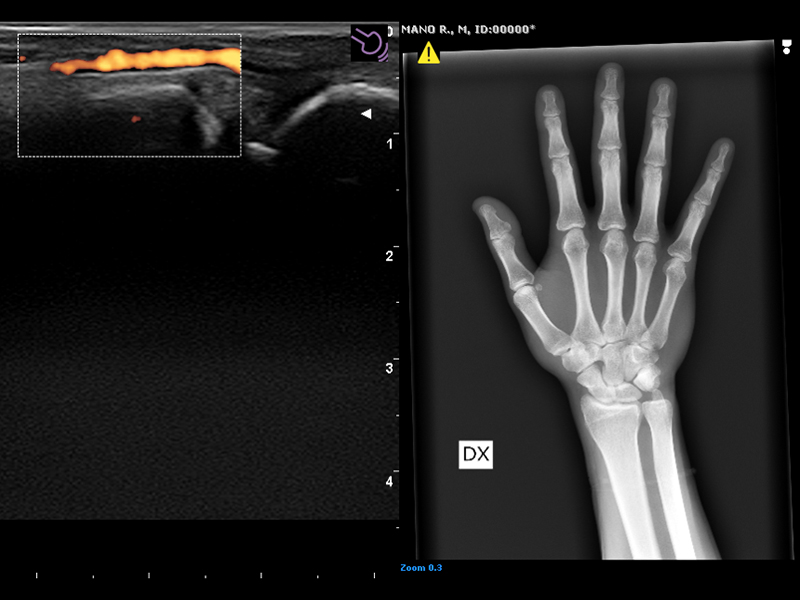

These procedures are often performed under ultrasound imaging guidance to increase accuracy and precision, such as in infiltrations where the brightness of the needle can be emphasized by using Esaote’s advanced Needle Enhancement tool. Virtual Navigator (VNav) is the Esaote technology for fusion imaging that enables US examiners to combine real-time ultrasound with datasets from second modalities to increase diagnostic accuracy and provide a more comprehensive understanding of a particular region of interest.

In MSK, fusion imaging between CT/MRI and US can be particularly valuable, for example for joint injections and biopsies.